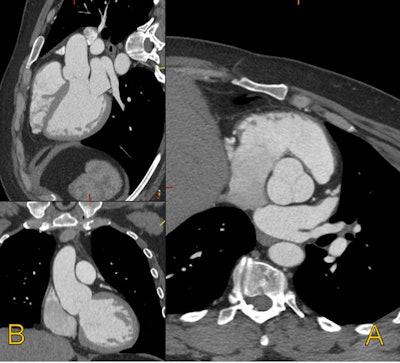

Aortic root dilation. Radiologically, aortic root dilation is typically the earliest and most critical finding. Diagnostic thresholds are generally set at greater than 40 mm for younger male patients and greater than 37 mm for younger female patients. These measurements must be made in a plane orthogonal to the axis of the aortic root to ensure accuracy. Measurements should be performed bidirectionally (as opposed to the cusp to commissure tridirectional measurement used with transcatheter valve planning) to mirror those obtained on echocardiography and studied in the literature.

A 33-year-old man with Marfan syndrome and dilated aortic root. On the transverse images (A) the aorta measures 4.5 cm by 4.2 cm. When corrected for long axis (B) of the aorta, the aorta measures 3.9 cm by 4.2 cm. Measurements obtained orthogonal to the long axis of the aorta allow for consistent sizing and accurate risk assessment. Volume rendered image shows the root dilatation with mild effacement of the sinotubular junction (see below). This phenotype is sometimes referred to as annuloaortic ectasia, a characteristic finding of Marfan syndrome. Additional axial and coronal images of aortic dilation are provided (see below). All images courtesy of Sanjeev Bhalla, MD, and Mensur Koso, MD.